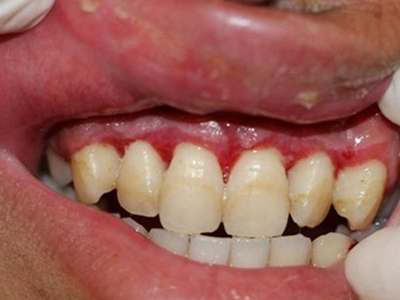

牙龈炎是发生于牙龈组织的炎症,患者可出现牙龈出血伴肿胀、发红、正常形态改变和偶尔不适等症状。本病主要由口腔卫生状况差导致,包括口腔不洁、牙菌斑等,诊断依据临床检查,治疗包括专业牙齿清洁和加强家庭口腔卫生。

牙龈炎可先引起牙齿与牙龈之间的沟(龈沟)加深,然后牙龈充血,炎症围绕一个或多个牙齿,伴牙龈乳头肿胀和易出血。一般无痛,可自行消退,也可维持轻度炎症数年。

牙龈炎常见的病因是口腔卫生差,不良的口腔卫生使牙菌斑沉积于牙齿与牙龈之间,造成龈沟加深,另外牙结石、不良修复体等也可造成牙龈炎的发生。

牙龈炎患者可通过改善口腔卫生控制疾病,同时使用抗菌漱口液,如复方氯己定含漱液,并进行彻底的洁治处理。必要时,重新修整修复体的不良外形,并祛除局部刺激因素。